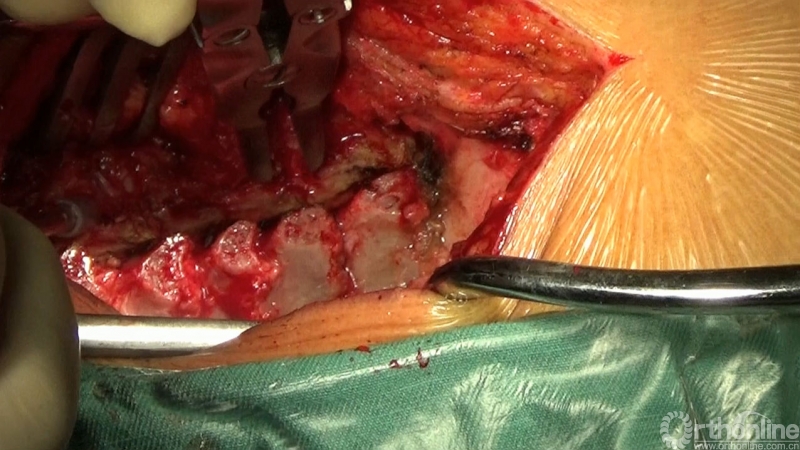

大会第一天,北医三院周非非副教授在“厚德仁“术”—前沿/经典手术视频详解”专题中,汇报了一例“保留一侧肌肉韧带复合体的颈后路单开门椎管扩大成形术”的经典病例,详细讲解了该术式的设计理念、操作步骤和注意事项,并就门轴断裂、椎板间融合、关门现象和C5神经根麻痹等重要问题与现场嘉宾进行了深入探讨。

手术体位:俯卧、屈颈、上身抬高、20-30°、臀部支撑

棘突截骨

显露

棘突打孔

对侧椎旁肌剥离

门轴部位

咬骨钳制备门轴

磨钻制备门轴

超声骨刀开门

椎板打孔

穿钛缆

固定钛缆

重建颈半棘肌

椎旁肌点对点缝合